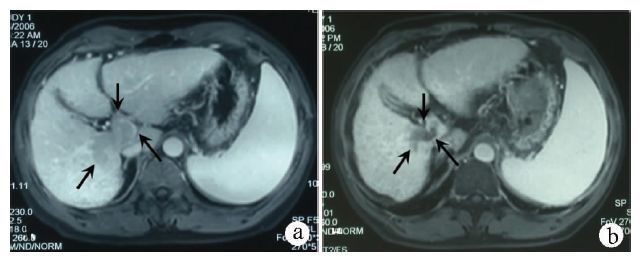

局限在肝内但不能手术切除的肝细胞癌患者,给予经肝动脉化疗栓塞(TACE)后结合外放疗,虽然受限于全肝的放射耐受剂量,达不到完全控制肿瘤,但放疗后肿瘤缩小,达到部分缓解,外科医生认为可以手术时,应该尽可能给予手术切除。笔者[1]曾报道,外放疗后,不能手术切除的肝癌患者转化为二期手术,手术切除率23%(8/35),手术标本有残存的癌细胞;接受手术的患者,较未能手术切除者的生存期长。同期临床资料[2]显示,单纯TACE获得二期手术切除率为12.8%(19/149),TACE结合外放疗二期手术切除率为20.4%(11/54)。病例1是大肝癌转化为小肝癌,获得手术切除机会(图1)。

注:a,介入后3周复查CT,肿瘤10.6 cm×5.8 cm,超过一半的肿瘤无碘油沉积;b、c,介入后1个月开始放疗,50 Gy/25次;d,放疗结束后7周复查CT,肿瘤缩小到5 cm,外科医生考虑降期手术;e,手术切除标本,可见鱼肉样残存癌组织;f, 术后50 d随访CT,切缘术后改变;g,术后1年随访MRI,未见肿瘤。迄今存活6年。

图1 不能切除的大肝癌降期后手术